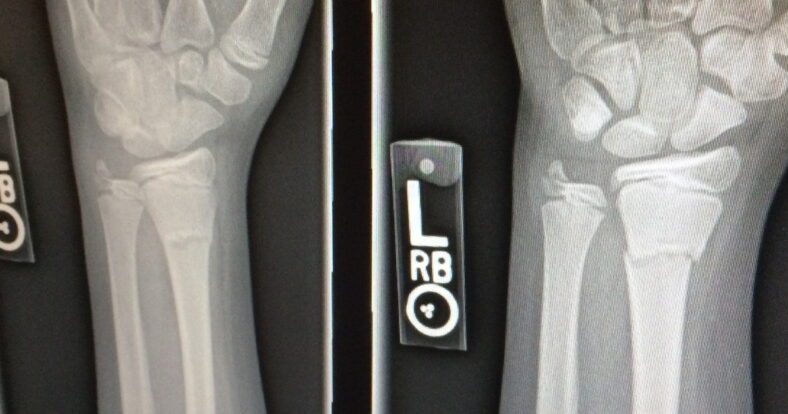

Schwache Knochen oder gar schon Beinbruch